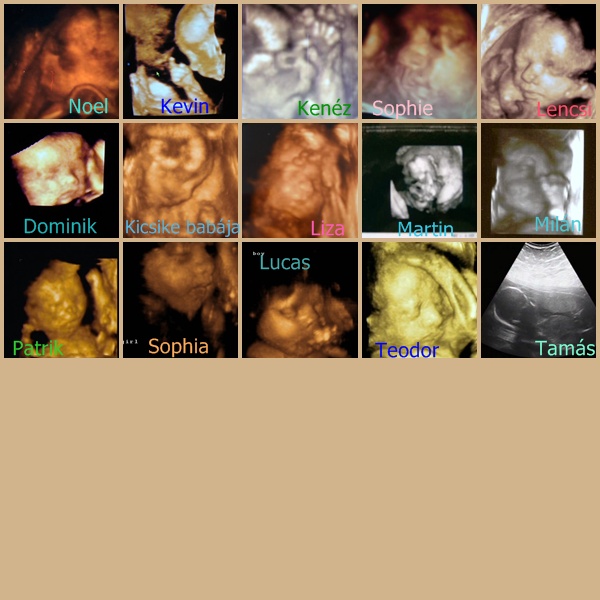

kopee: örülök, hogy minden koé. A blogod tök jó és a képek fantasztikusak!